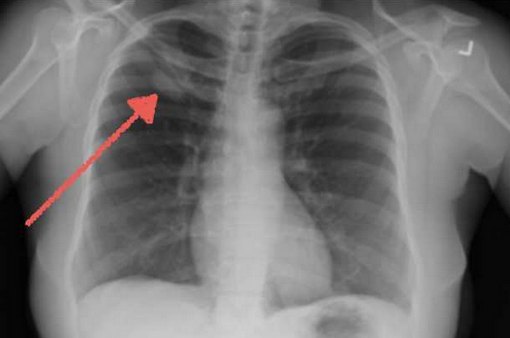

- Центральный рак легкого характеризуется поражением прикорневых отделов легкого, поражает бронхи крупного калибра (главные и долевые). Это приводит к сужению просвета бронха, нарушению его дренажной функции и, следовательно, спадению легочной ткани (ателектазу). Ателектазы зачастую осложняются пневмонией, что может маскировать и затруднять диагностику опухоли.

- Рентгенография органов грудной клетки (наиболее доступный метод при меньшем облучении в сравнении с флюорографией)

- Визуализационных методов исследования. На рентгенограмме лёгких просматриваются периферические участки инфильтрации с признаками опухолевого роста. КТ и МРТ грудной клетки помогают уточнить локализацию новообразования, выявить метастазы в регионарных лимфатических узлах, контрлатеральном лёгком. МРТ, ПЭТ КТ и остеосцинтиграфия применяются для определения удалённых секундарных изменений.

Неинвазивные методы диагностики — это рентгенография органов грудной клетки, КТ и МРТ, УЗИ. Инвазивные методы — это трахеобронхоскопия (исследование бронхиального дерева — хорошо визуализируется центральный рак), торакоскопия (исследование плевральный полостей — хорошо визуализируется периферический рак), медиастиноскопия используется для исследования лимфатических узлов переднего средостения, диагностическая торакотомия — завершающий метод диагностики распространенности опухоли при неэффективности других, пункционная биопсия опухоли — обязательная процедура при всех инвазивных методах исследования.